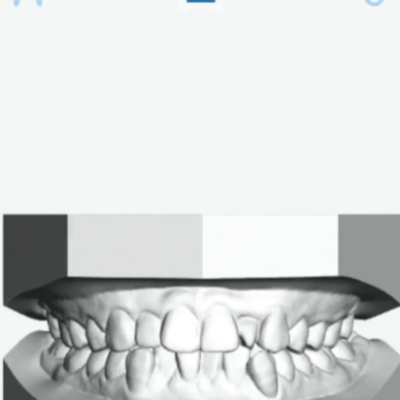

培训日期: 2026-03-06 视频内容:介绍了软件版本eSet4.01的升级内容,主要介绍了新增的核心功能——非节点分布算法。视频详细讲解了如何使用新算法进行牙齿移动路径的设计,包括选择分布算法、...